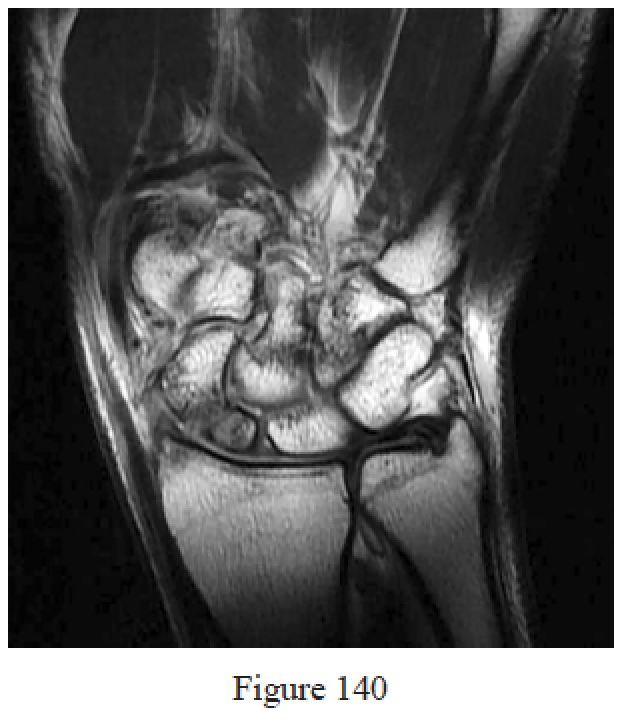

Figure 140 is the T1-weighted MR image of a 24-year-old man who has a 6-month history of right wrist pain. He fell on an outstretched hand while skateboarding 18 months ago and had pain that resolved after several weeks. Radiographs of his right wrist demonstrate an established scaphoid nonunion at the waist with a humpback deformity and no signs of arthritis. What is the best next step?